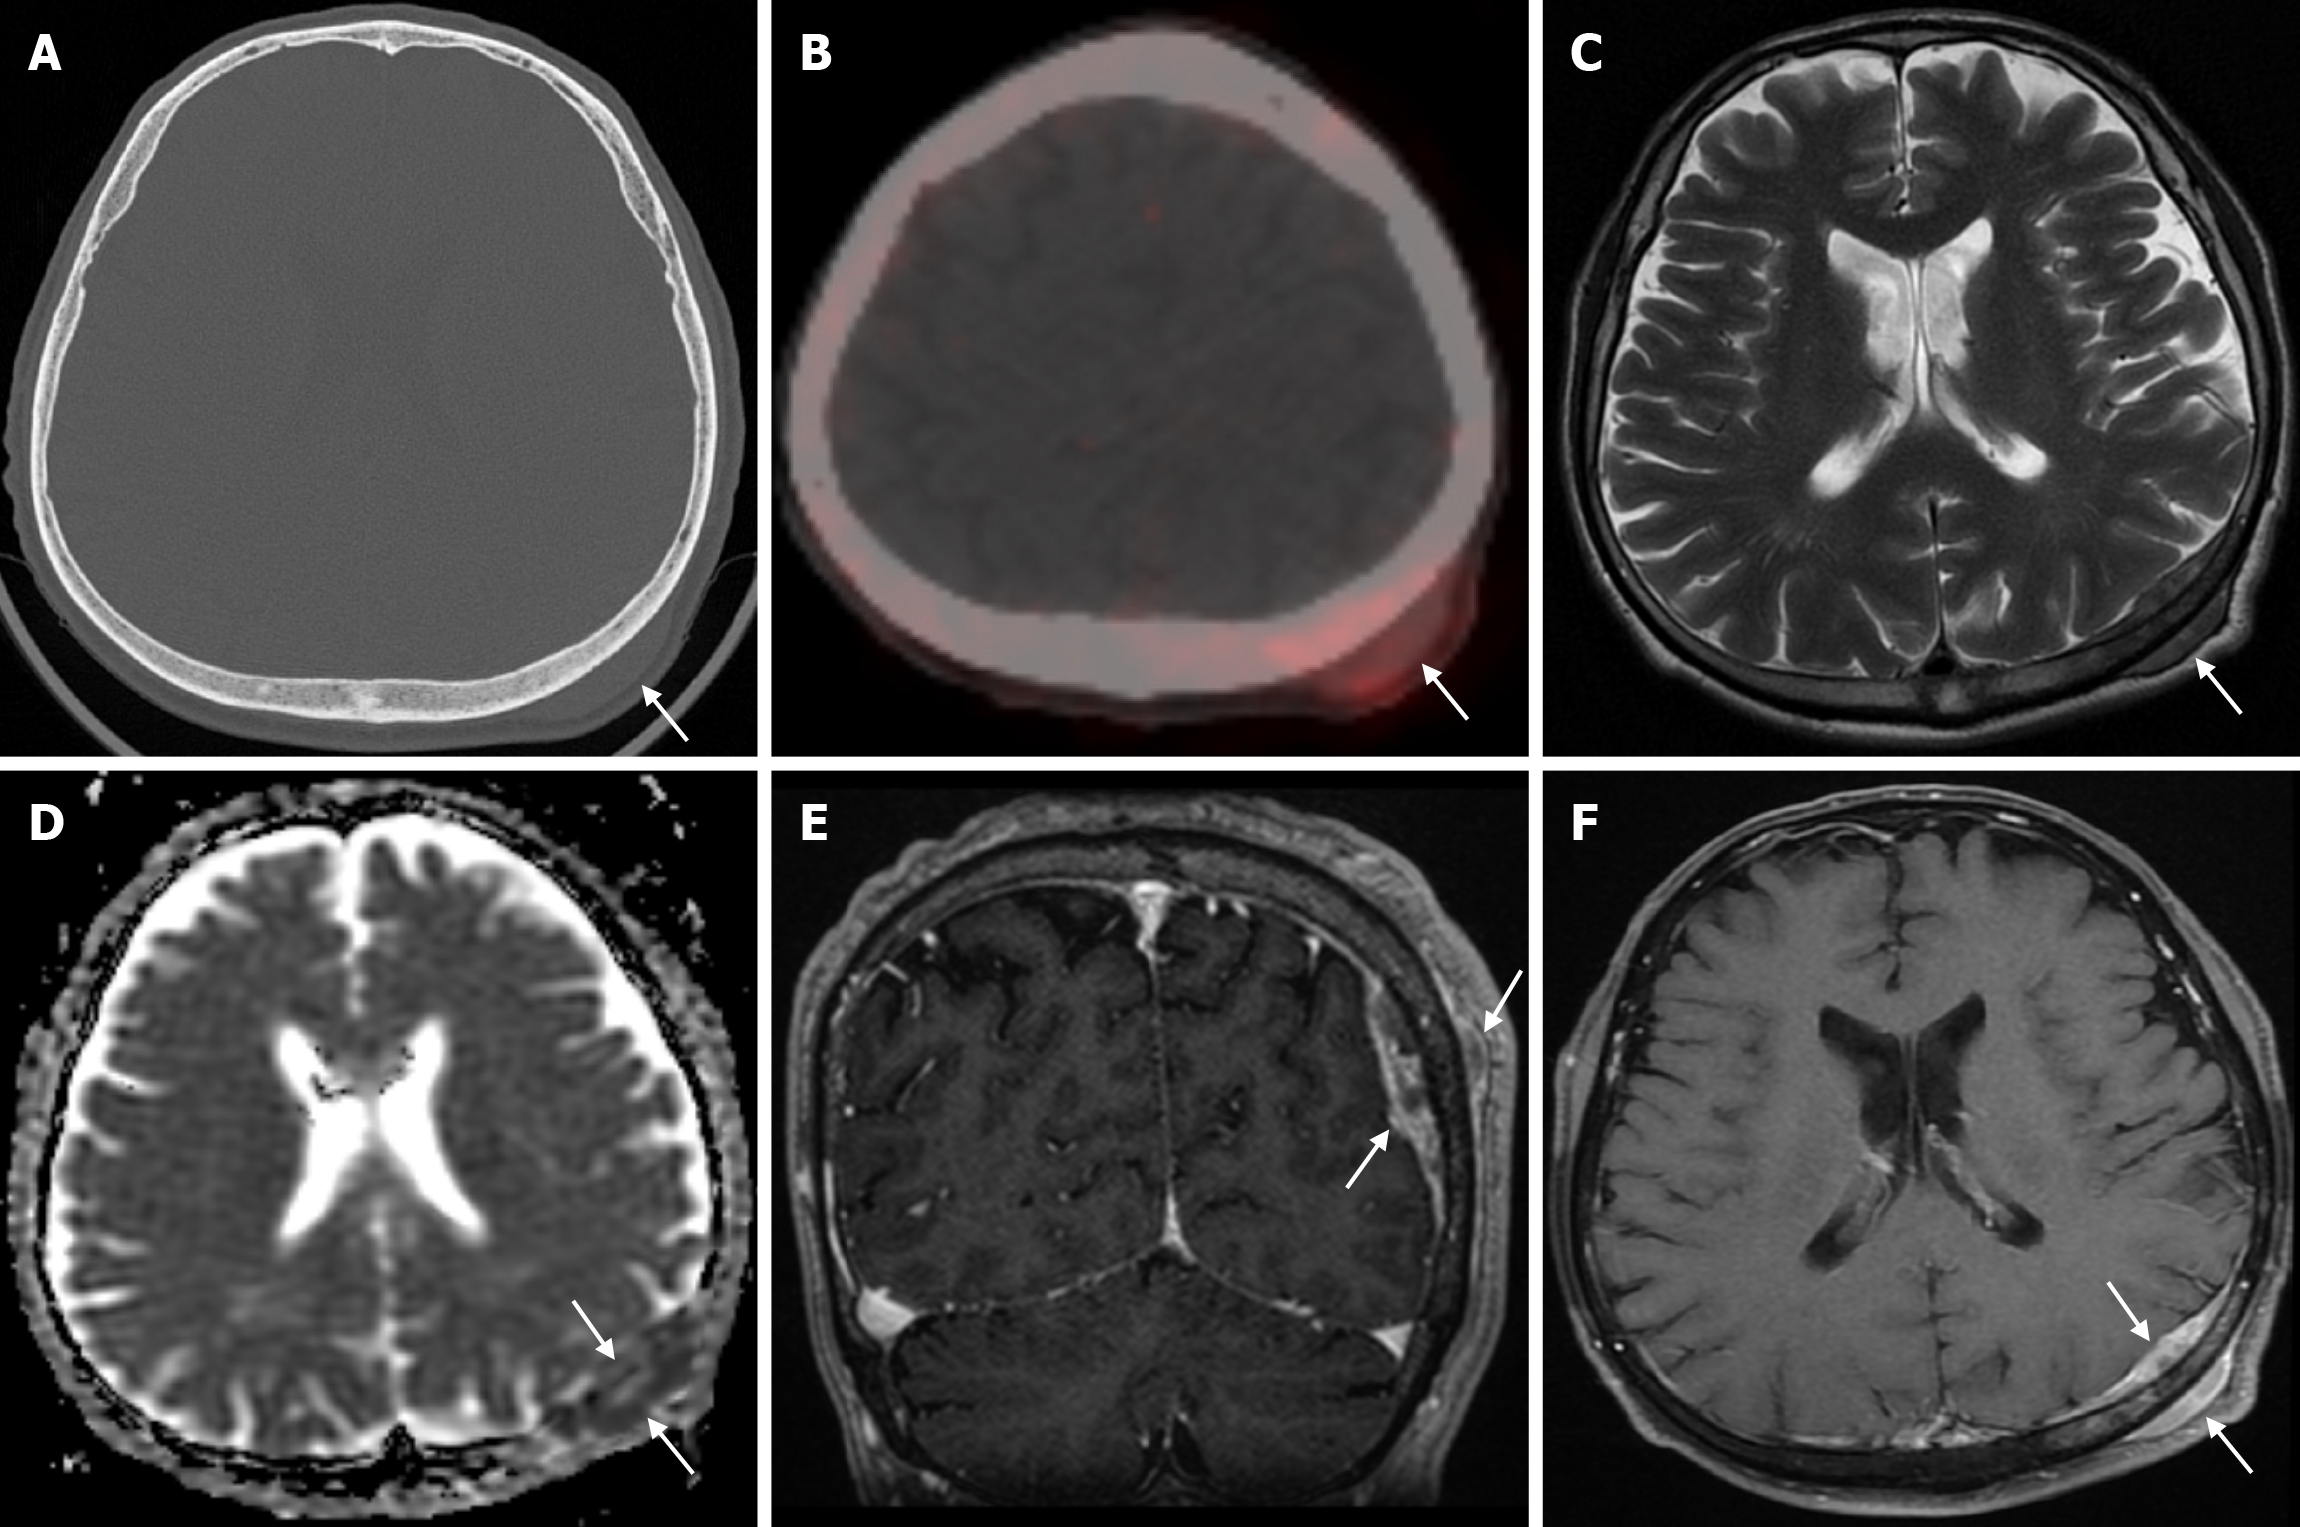

Arachnoid granulations (Pacchionian granulations) are cerebrospinal fluid-filled projections that extend from the subarachnoid space through openings in the dura into the venous sinuses and can be seen macroscopically. Their incidence varies from 0.3% to 55%. Arachnoid granulations are usually seen in millimeter dimensions, but may grow to fill the dural sinuses or arch the inner table[11]. In addition, intraosseous arachnoid granulations can sometimes extend to the inner table of the bone, causing scalloping, remodeling or bone erosion of the inner table[12]. The prevalence of arachnoid granulations increases with age, but there is no difference in gender distribution. Arachnoid granulations with a slight left hemispheric predominance are found in the dural venous sinuses, most frequently in the transverse sinuses and especially in the middle or lateral parts. The second most common location is the superior sagittal sinus, but they can be found anywhere in the dural venous sinuses. Arachnoid granulations are usually detected incidentally. If they fill and expand the dural sinuses, causing partial sinus obstruction, they may cause symptoms of increased intracranial pressure due to venous hypertension. They are usually associated with headaches. Arachnoid granulations may be seen as radiolucent areas on plain radiography of the skull or may cause compression on the inner table of the skull. On CT imaging, arachnoid granulations can be seen as sharply demarcated, hypodense structures in close relation to the dural venous sinus. On MRI, they usually show hyperintense signal on T2-weighted images and hypointense or isointense signal on T1-weighted images compared to brain parenchyma (Figure 1). On CT angiography, MR angiography or catheter angiography imaging, arachnoid granulations appear as oval or round filling defects in the dural venous sinuses during the venous phase[11]. Recent advances in radiology have made it possible to identify brain herniations into the arachnoid granulation by improving image quality with higher resolution and thinner slice three-dimensional T1-weighted and T2-weighted MRI sequences (Figure 2). Brain herniation into the arachnoid granulation is rare in the literature, and the incidence of brain herniation into the calvarial or dural sinuses has been reported to be 0.32%[13]. Arachnoid granulations may be confused with pathological processes in the dural venous sinuses[11]. In the differential diagnosis of arachnoid granulations, venous sinus thrombosis, dural-based tumors, or structures such as septa and fat that may cause filling defects in the dural venous sinuses should be considered[12]. Dural sinus thrombosis usually fills an entire sinus segment or several sinuses and may extend to the cortical veins, whereas arachnoid granulations appear as focal and well-defined defects. Fresh thrombus in the dural sinuses are hyperdense on CT and hyperintense on T1-weighted MRI. Differential tumor diagnosis can be made based on its shape, lack of contrast enhancement and diffusion restriction[11].

Epidermoid cysts are small or medium-sized, benign, and slow-growing tumors that arise from the remnants of ectodermal cells in the bones of the skull. These cysts can also develop after trauma or surgery. Epidermoid cysts are lined with squamous epithelium. They contain deposits of cholesterol and keratin. These cysts constitute less than 1% of primary intracranial tumours, while intradiploic epidermoid cysts account for less than 0.25% of intracranial tumours. These tumors can occur at any age from the first decade of life to the seventh decade, with a mean age of 32-38 years, and there is no gender predilection. Epidermoid cysts are most commonly found in the frontal, parietal and occipital regions and often involve more than one bone. Epidermoid cysts appear on plain radiography as round or lobulated lytic areas with smooth and sclerotic margins. On CT they appear as non-contrast enhanced intradiploic lytic hypodense lesions with smooth sclerotic borders. Epidermoid cysts often cause remodeling and widening of the inner and outer tables. Epidermoid cysts that appear hyperdense on CT due to bleeding, calcification or high protein content are called white epidermoids and are observed quite rarely. On MRI, epidermoid cysts appear isointense/hyperintense on T2-weighted and fluid-attenuated inversion recovery (FLAIR) images and slightly hyperintense on T1-weighted images (Figure 4). These lesions restrict diffusion on diffusion-weighted imaging but show no contrast enhancement on contrast enhanced sequences[19].